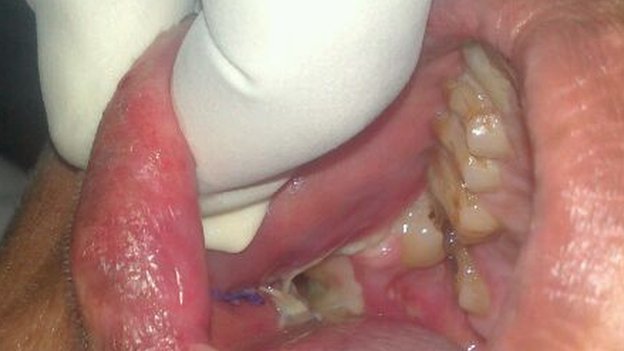

Ashik Gavai را با تورم در فک راستش آورده بودند. مشکل او یک نوع تومور خوشخیم تشخیص داده شد.

در ابتدا ما نمیتوانستیم دندانهای اضافی او را خارج کنیم تا اینکه برای خارج کردن آنها مجبور به استفاده از basic chisel و hammer (چیزل و چکش) شدیم. هنگامی که فک شکافته شد دندانها مانند مرواریدهای کوچک شروع به بیرون آمدن کردند، در ابتدا ما آنها را که واقعا مانند مرواریدهای سفید کوچک بودند جمع میکردیم اما پس از مدتی خسته شدیم! ما در نهایت تعداد ۲۳۲ دندان که اضافه شده بودند را شمارش کردیم.

Ashik حالا ۲۸ دندان دارد و مجبور به تحمل هفت ساعت عمل جراحی روی دندانش شد.

فطعات خارج شده از فک این نوجوان نه ۲۳۲ دندان، که ۲۳۲ قطعه با ساختاری شبیه ساختار دندان هستند.